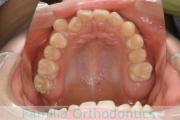

上顎

下顎